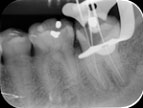

- Chân răng cong, dễ gẫy dụng cụ trong quá trình thao tác, ngoài ra khó làm sạch và tạo hình

Chân răng cong và dài là một trong những thách thức với điều trị nội nha.